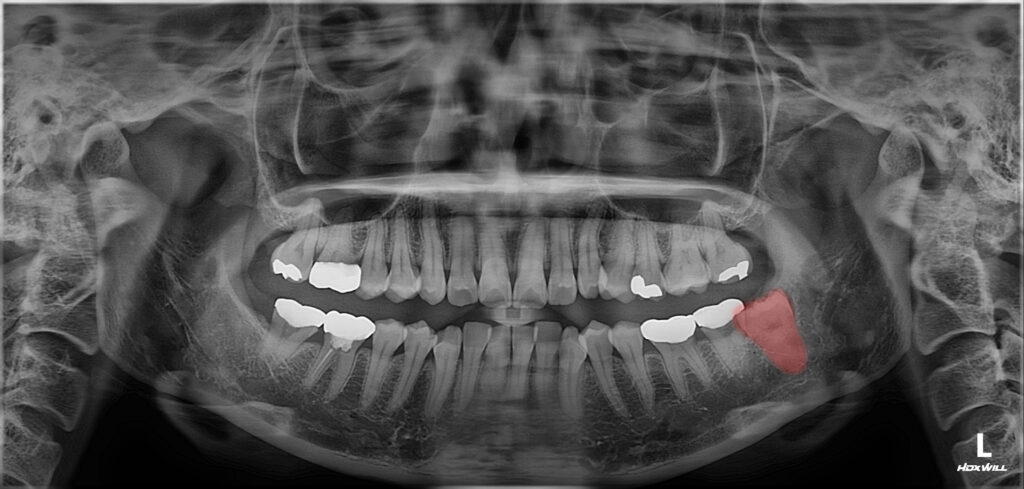

위 환자분께서는

왼쪽 아래 매복 사랑니가 있는데

옆 치아에 문제가 생길까 싶어

발치를 희망하셨어요.

해당 사랑니는 턱뼈 안에 완전히

매복되어 있는 상태였으며,

이로 인해 주변 치아에

지속적인 압력이

가해지고 있었어요.